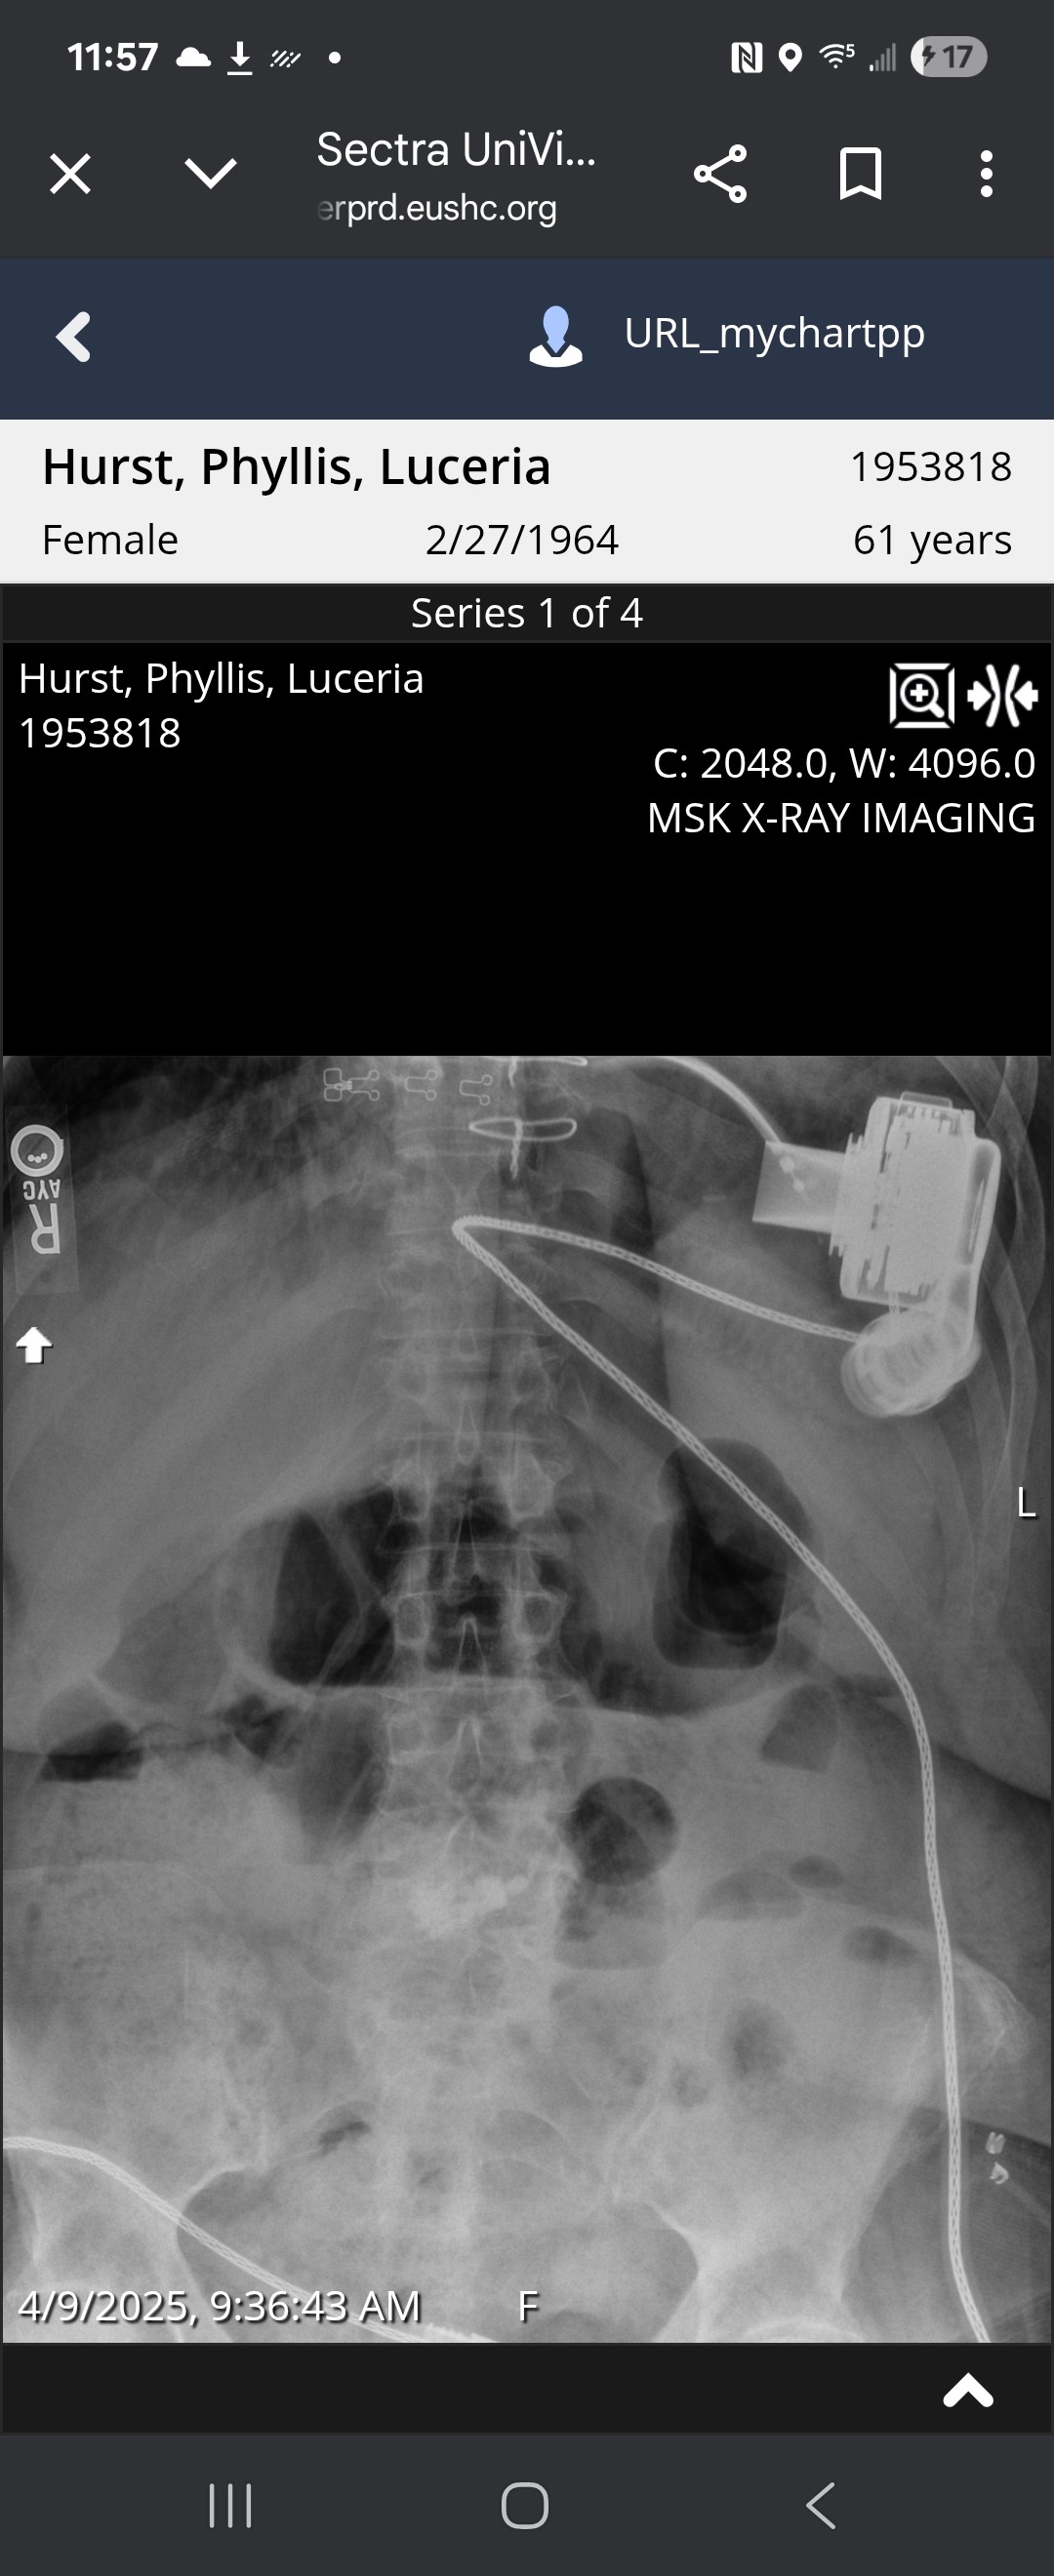

As many of you know, I recently underwent LVAD (Left Ventricular Assist Device) surgery—a major and life-saving procedure that now helps my heart move blood more effectively with the use of a battery powered pump. It’s been a challenging journey physically, emotionally, and financially, but I’m deeply grateful to be here and moving forward, one step at a time.